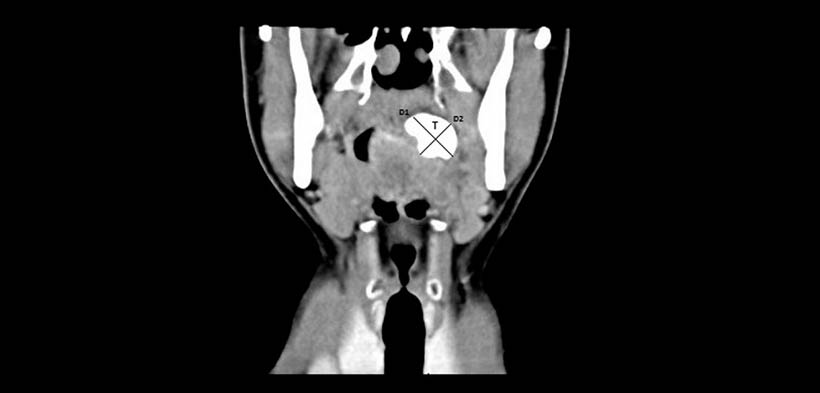

Fig. 1. Tomografía computarizada (TC) vista coronal que muestra una masa hiperdensa (T) en la región periamigdalino izquierdo. Mide aproximadamente 30x20mm (D1xD2).